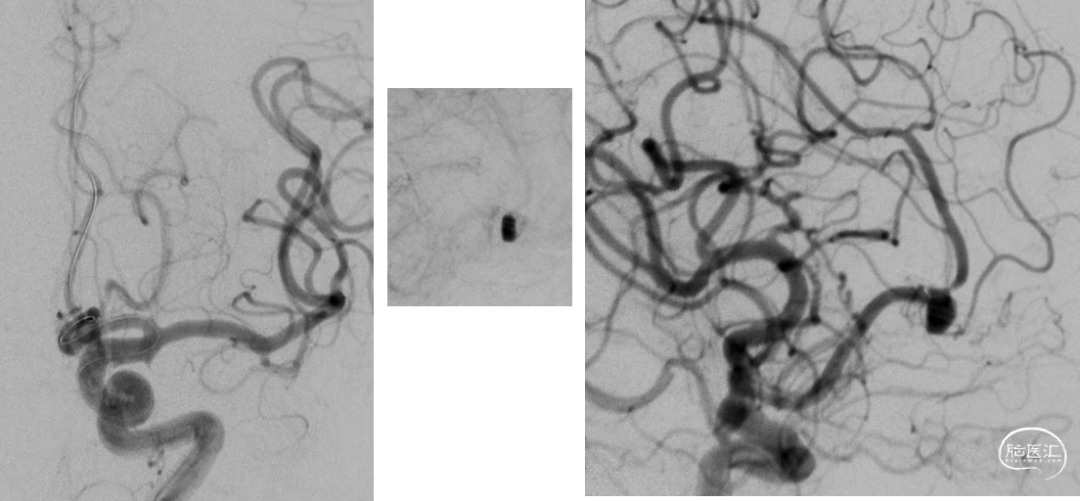

DSA

平均宽度(4.5+3.8)=4.2mm,最小深度7.5mm,选择SL5x3

微导管到位动脉瘤腔

通过VIA17释放web

造影可见造影剂滞留

手推造影-推挤-造影

解脱web

术后正侧位造影

术后CBCT